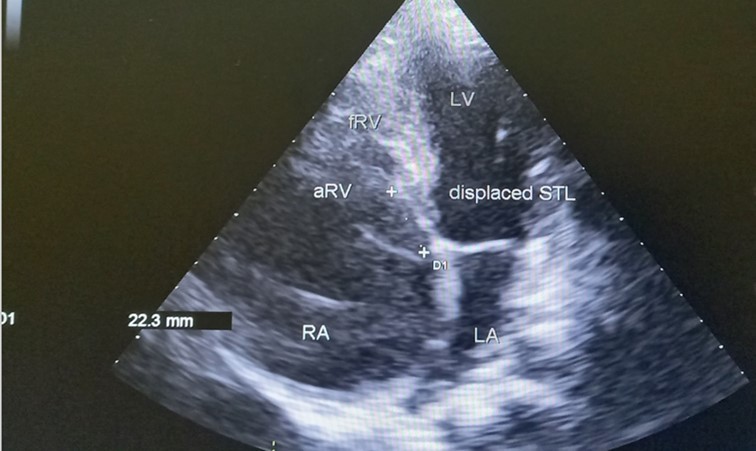

The patient underwent echocardiography (Figure 3 ) showing a low insertion of the septal and posterior leaflets of the tricuspid valve 22 mm below the tricuspid annulus, the anterior leaflet having reduced reduced mobility. Significant dilatation of the the right atrium by atrialisation of the right ventricle (RV). The rudimentary RV and its atrial stump are dilated and responsible for compression of the LV. There was no tricuspid insufficiency. No other associated congenital anomaly. However, we found a large floating thrombus in the right atrium measuring 64 mm x 30 mm in diameter. This was therefore Ebstein's disease at stage C of the Carpentier classification. The apical displacement of the tricuspid septal valve was 22 mm or 15 mm/m2). The surface area of the atrium and the atrialized right ventricle was 45 cm2 , the surface area of the right ventricle and the left cavities was 30 cm2 , the Celermajer index was calculated at 1.4 ( Grade 3).

Figure 3.Transthoracic echocardiography, apical four chambers view . Apical displacement of the tricuspid valve (a) and right atrial thrombus (b).

Echocardiography is an essential diagnostic test and allows accurate assessment of the tricuspid valve leaflets and the size and function of the heart chambers. The main feature of Ebstein’s anomaly is an apical displacement of the tricuspid septal leaflet of at least 8 mm/m2. The average displacement in our patient was 15 mm/m2

Celermajer et al described an echocardiographic grading score for neonates with Ebstein’s anomaly, extended Glasgow Outcome Scale, with grades 1 to 4. The ratio of the combined area of the right atrium and atrialized right ventricle is compared with that of the functional right ventricle and left heart (ratio <0.5, grade 1; ratio of 0.5 to 0.99, grade 2; ratio of 1.0 to 1.49, grade 3; ratio ≥1.5, grade 4) 8, 11.

In our case, the patient had, type C of EA and Grade 2. The investigation also revealed a large thrombus floating in the right atrium and no obvious regurgitation of the tricuspid valve. In addition, the septa was intact, there was no persistence of the ductus arteriosus, the pulmonary and aortic pathway were unobstructed.